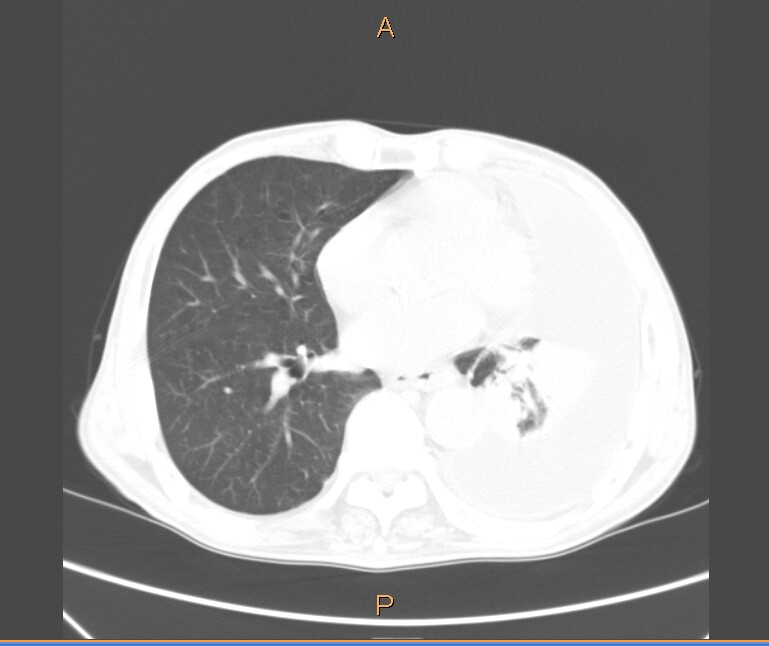

男,81岁。咳嗽、气短伴上腹部不适感。

左肺大量胸腔积液,压迫性肺不张。伴左肺膨胀不全。胃窦怀疑占位,建议胃镜

左肺大量胸腔积液,压迫性肺不张。伴左肺膨胀不全。肝右后叶囊肿、双肾囊肿。胃窦怀疑占位,建议胃镜